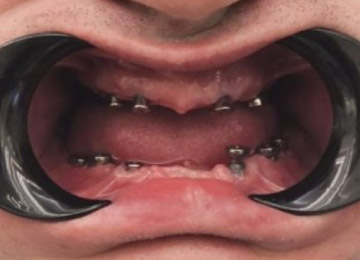

Имплантация зубов: фото "До" и "После"

Фото ДО

Фото ПОСЛЕ

Наведите для просмотра

All-on-4